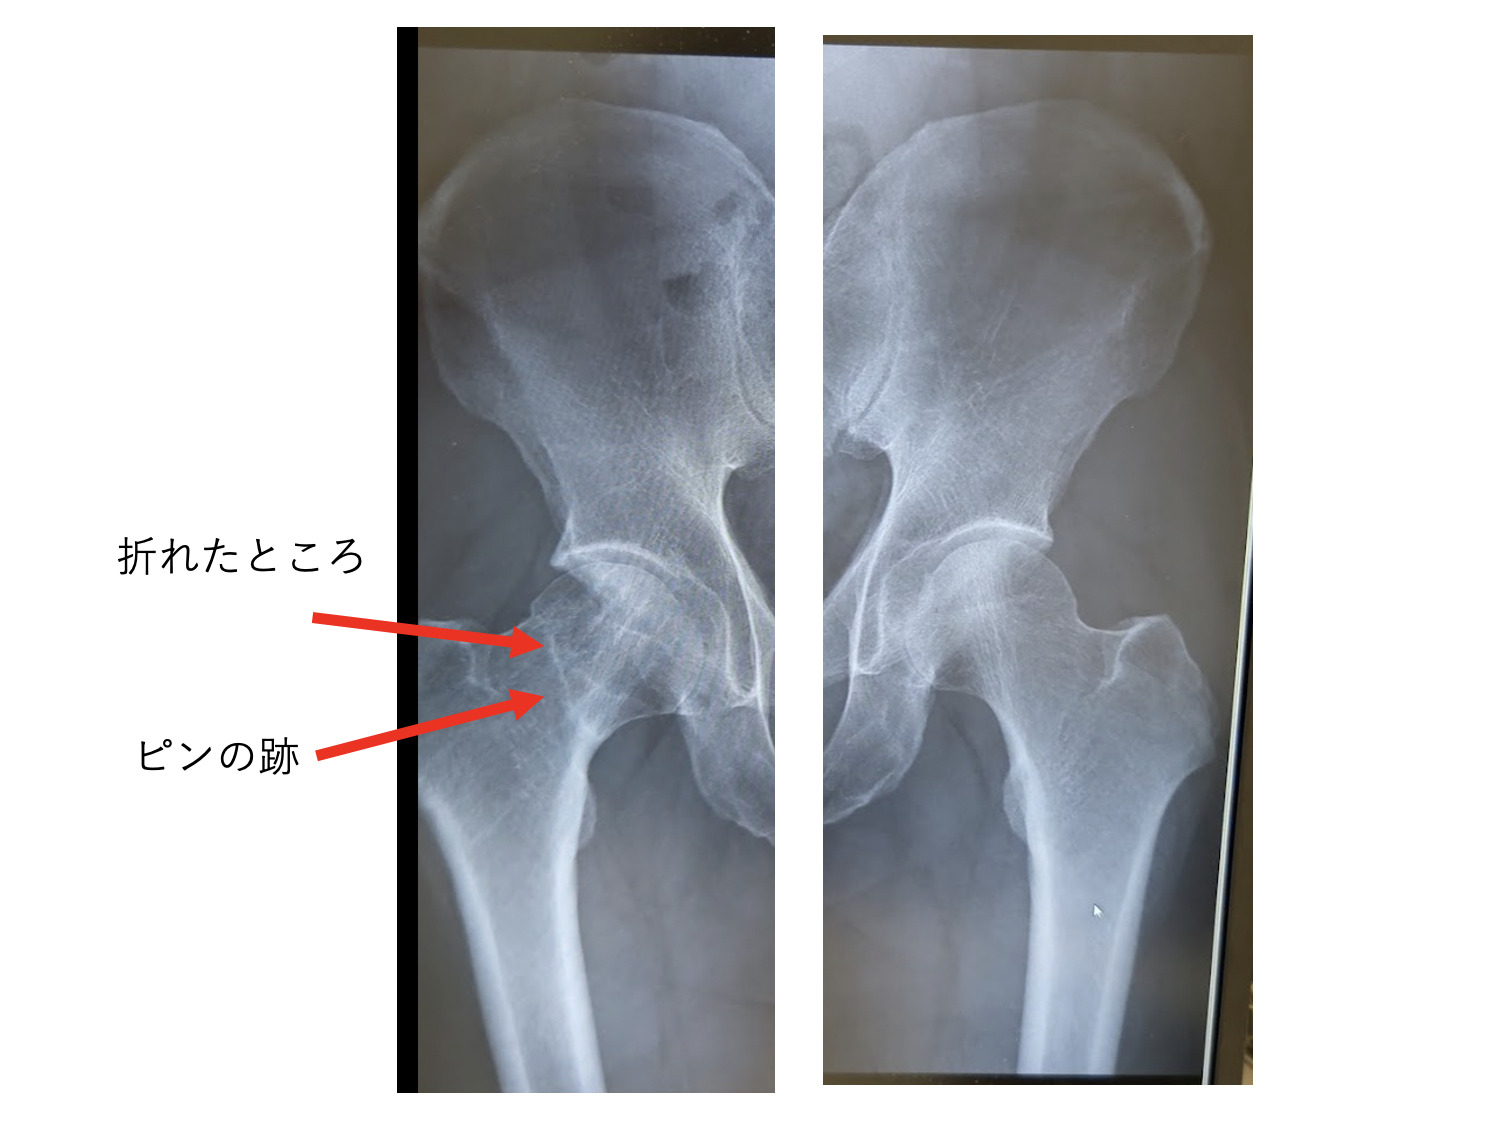

2019年6月5日に交通事故にあい、大腿骨頸部骨折で3ヶ月入院。

骨折は、骨頭壊死になると人工骨頭となりバイクができない=トライアスロンができないという可能性がありました。

今後100%大丈夫ともいえないので、「可能性があります」が正しいのかもしれませんが。

2021年9月に骨折部位をとめていたピンを除去する手術(6日&退院後1ヶ月松葉杖)。

2022年3月22日の診察でランOKとなりました。

最新のレントゲンをみると、右のほうが短くなっています。

折れたところがくっつくと、そうなるようで、しかたないとのこと。

元通りにはならないとのことです。

右のほうが短いということは、それなりの支障はあるでしょう。

折れたところの線、ピンの跡も消えないとのこと。

なんかこう見ると、ここがまた折れたら……とか思ってしまいます。

医師の話だと、「折れることはないけど、くっつかないことはあるとのこと」。

「くっつかない」というのは、今後何をしても変わらないですし、何もしなくても変わらないということです。

手術した医師(転院したので今は違う医師)も、「折れたときに運命は決まっている」とおっしゃっていました。

こんなふうにピンで固定して、絶対安静でした。